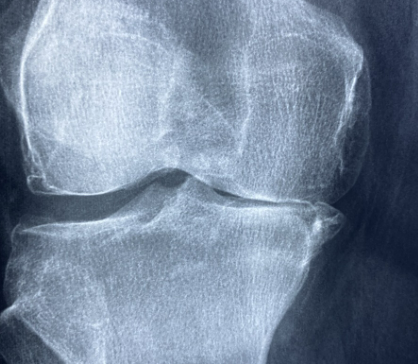

여러분, 무릎이 찌릿하고 계단 오를 때 ‘아이고~’ 소리가 절로 나온 적 있으신가요? 저도 50대를 넘어서면서부터 무릎이 조금씩 좋지 않다고 많이 느끼고 있습니다. 특히 등산을 좋아합니다. 무릎 연골이 빨리 닳을 수 밖에 없는 취미를 하고 있었던 것이죠. 더욱 그래서 요즘 ‘관절 건강’에 많은 관심을 가지게 되었습니다. 그러다가 우연히 TV 건강프로그램에서 알게 된 게 바로 철갑상어 콘드로이친입니다. 집에도 이미 이전에 구입해 놓은 콘드로이친이 있어서 콘드로이친이 다 똑같은 것으로만 알았는데 어디서 추출한 것이냐에 따라 성분과 효과가 다르다는 것을 알게 되었죠.

콘드로이친은 원래 우리 몸속 연골, 힘줄, 인대 등에 존재하는 천연 성분입니다. 쉽게 말해 관절 사이에서 뼈끼리 부딪히지 않도록 완충 역할을 해주는 거죠. 그런데 나이가 들거나 운동을 과하게 하면 이 성분이 줄어들면서 관절 마찰이 생기고 통증이 시작됩니다. 그래서 요즘 관절 영양제엔 콘드로이친이 빠지지 않고 들어갑니다. TV를 보면 하루에 한 두번은 이 콘드로이친 광고를 접하는 것 같습니다.

콘드로이친은 C6S형과 C4S형으로 나뉘는데, 건강한 성인 남성은 C6S의 비율이 높고, 관절염 환자는 C4S의 비율이 높습니다.

C6S와 C4S의 비율이 퇴행성 관절염 환자와 류마티스 관절염 환자의 경우 정상인에 비해서, C6S형의 콘드로이친이 훨씬 적다는 임상 결과가 있습니다. 건강한 상태에서 C6S형은 C4S형보다 약 5배 이상 정도로 많아야 하지만 퇴행성 관절염 환자나 류마티스 환자는 C4S가 더 많은 것입니다.

그러니까 C4S와 C6S의 비율이 소의 경우 2:1, 상어가 0.7:1, 철갑상어가 0.22:1로 철갑상어의 C6S의 비율이 높아 건강한 성인의 비율과 비슷한 것으로 나타났습니다. 소의 경우 C4S의 비율이 더 높은 것을 볼 수 있습니다.